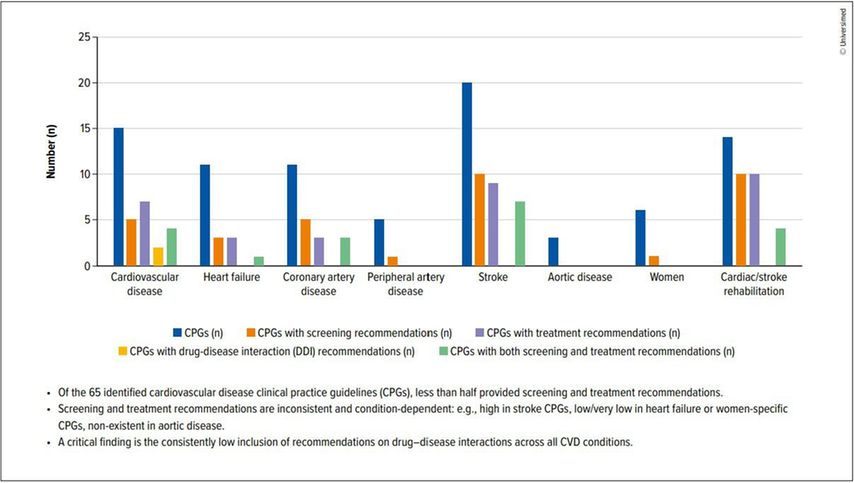

Clinical practice guidelines are designed to translate evidence into standardized, actionable recommendations. In areas such as diabetes, hypertension, and dyslipidaemia, guideline-directed care has transformed outcomes. Yet, the picture is markedly different when it comes to depression in CVD (Fig.1).6 Our review of 65 CVD guidelines across five continents revealed a gap between recognition of depression as a risk factor (71%) and provision of guidance: Only 23% included both screening and treatment recommendations (37% screening; 34% treatment), fewer than 3% addressed drug–disease interactions, an important concern given the high prevalence of polypharmacy in this population. Notably, just 12% involved mental health specialists in their development.6 Entire CVD areas, such as peripheral artery disease (PAD) and aortic disease, were almost silent on the issue of depression (Fig.2).6 Where recommendations existed, they varied widely in scope, specificity, and evidentiary strength. Screening was often encouraged, typically using PHQ-2 or PHQ-9, but without practical advice on implementation.6 Treatment recommendations ranged from psychotherapy and physical activity to SSRI, yet supporting evidence was often graded as low to moderate.6 Few guidelines addressed drug–disease interactions, despite polypharmacy being common in this population.6 This lack of systematic, high-quality guidance perpetuates underdiagnosis and undertreatment, leaving clinicians uncertain and patients at risk (Fig.3).

Fig. 2: Depression in clinical practical guidelines (CPGs): a frequently overlooked risk factor (see Armon DB et al. 2025)6

Fig. 3: Depression: a frequently overlooked condition in cardiovascular disease (CVD) guidelines (see Armon DB et al. 2025)6